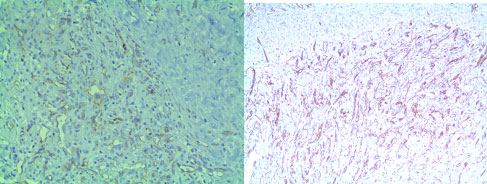

On microscopic examination, there were cavernous vascular spaces, solid spindle cells attached to vessel walls and vacuolated epitheloidendothelial cells [Table/Fig-5,6]. The lesion was well circumscribed, highly cellular with vascular proliferation and slit like spaces [Table/Fig-5,7]. There were few lymphocytes and eosinophils. Larger thin walled vessels with RBCs and areas of hemorrhage were also appreciated. The lesion did not show any cellular atypia and was well circumscribed without infiltration to surrounding structures. Histopathological diagnosis of vascular lesion i.e., spindle cell haemangioma was given. Immunohistochemistry (IHC) was done for the markers CD- 34 and CD- 31 for evaluation of origin of these spindle cells which were triple positive. Pericytes with surrounding blood vessels, split like vascular spaces lined by endothelial cells were positive for CD-34 and cells in vascular channels near endothelial lining were positive for CD 31 [Table/Fig-8] [1].

H&E 4X Histopathology slide showing dilated vascular spaces adjacent to solid spindle cell areas

H&E 40X Histopathology showing epitheloid enodethelial cells with vacuolations

H&E (10X) Histopathology slide showing spindle to epitheloid endothelial cells with slit like spaces within proliferations

IHC (10X) CD-31,CD-34 Immunohistochemical markers showing positivity inspindle cells and cells lining vascular channels